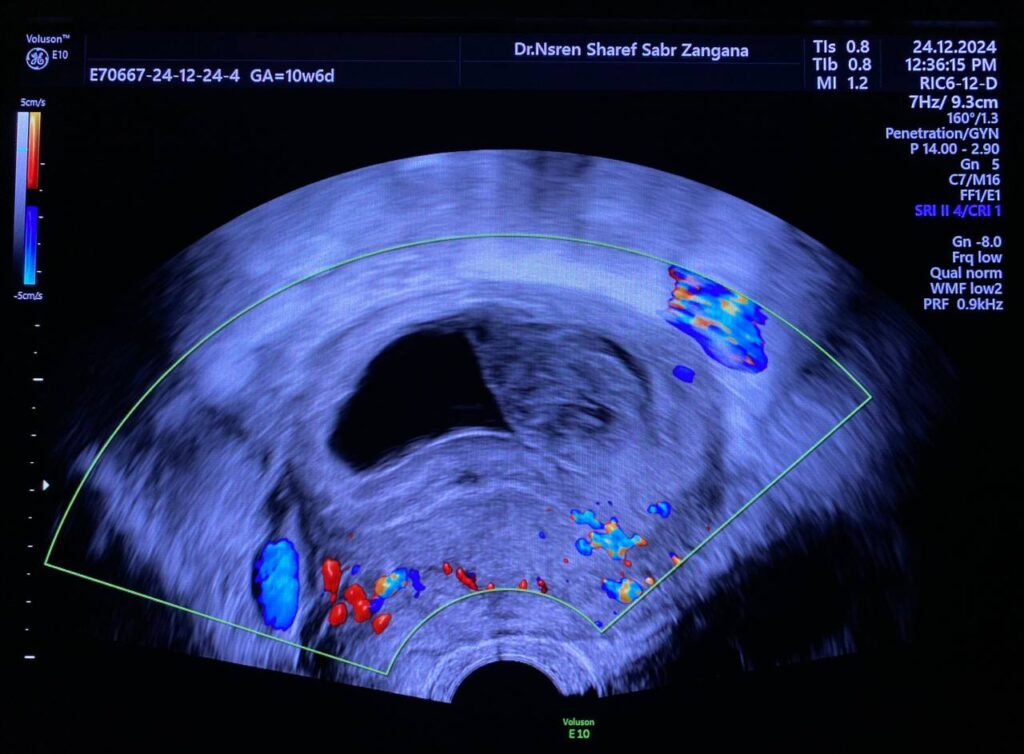

small collapsed fetal pole ( viability not seen )

because of few cytsic changes of placenta Hydatiform Mole should be excluded

small collapsed fetal pole ( viability not seen )

because of few cytsic changes of placenta Hydatiform Mole should be excluded